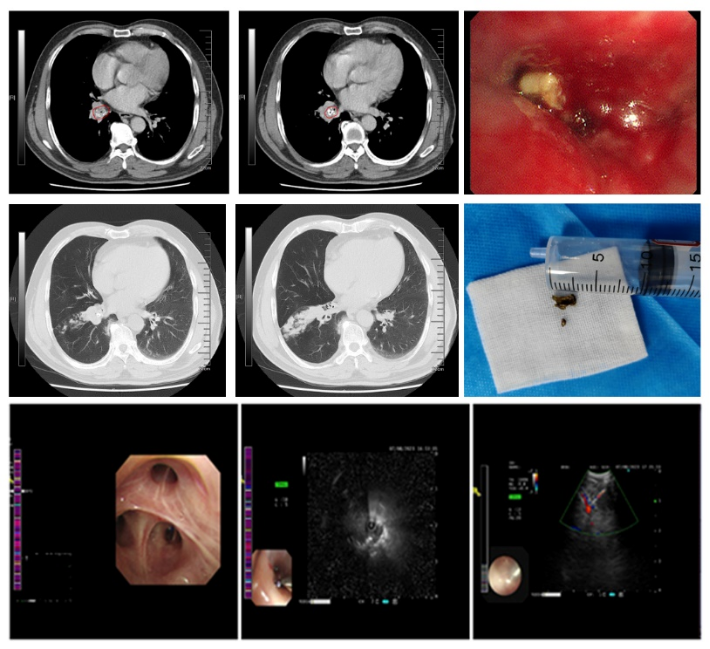

在张明医生的带领和指导下,洛阳市中心医院呼吸与危重症医学科开展支气管镜下介入治疗:如开展良性气道狭窄的球囊扩张、R/C-EBUS、支气管镜下肿物电圈套治疗、支气管镜下电刀切开+球囊扩张+冷冻、支气管镜下异物取出术等镜下操作,并取得了良好的治疗效果。